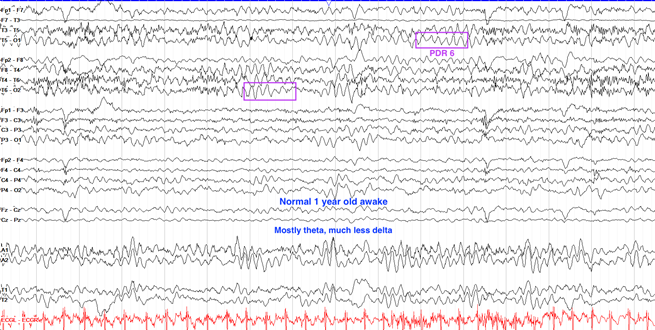

婴儿出生第一年的脑电图特征主要是大量缓慢、高振幅的δ波活动,这些记录应是连续且对称的。在婴儿2至4个月大之前,脑电活动不受睁眼状态影响;而在大约6个月大时,清醒状态下开始出现4至5赫兹的后放电反应。随着婴儿接近一岁,θ波逐渐加入到脑电活动中。困倦状态下,脑电背景依旧非常缓慢和高振幅,特别是在初期,常见1至2赫兹的波动,振幅可达200微伏。到了一岁时,清醒状态下的后放电反应频率增加到约6赫兹。这一系列变化体现了婴儿大脑发育的正常过程。

婴儿期(1-12个月)

1.正常发育模式